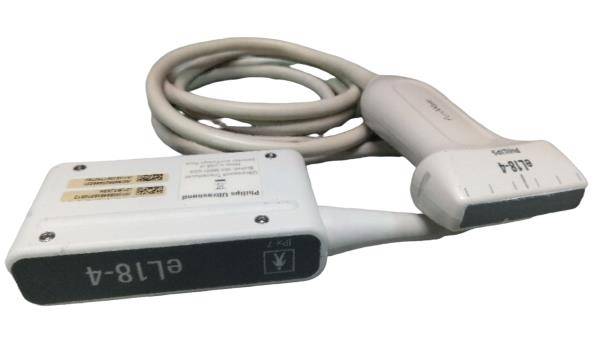

Linear Abdominal |